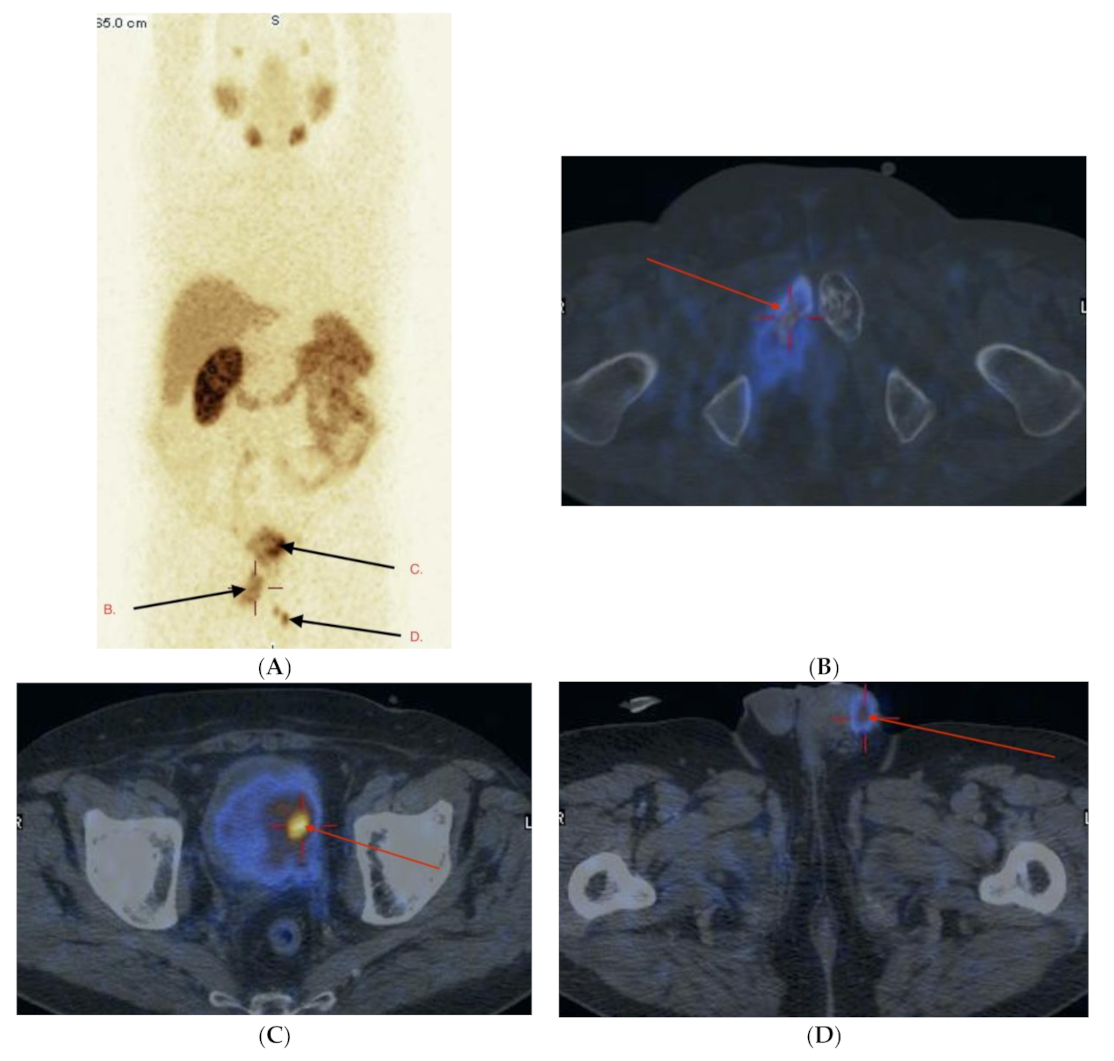

2.3. Imaging Studies

2.4. Detection of Active Pathology in Patients